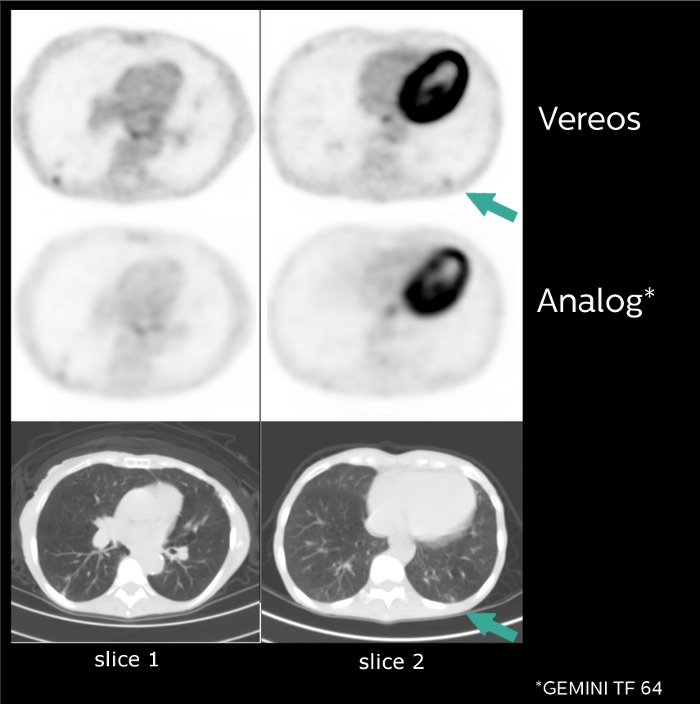

Sample images acquired in a clinical study of the Vereos PET/CT system at The Ohio State University. Investigational device limited by law to investigational use.